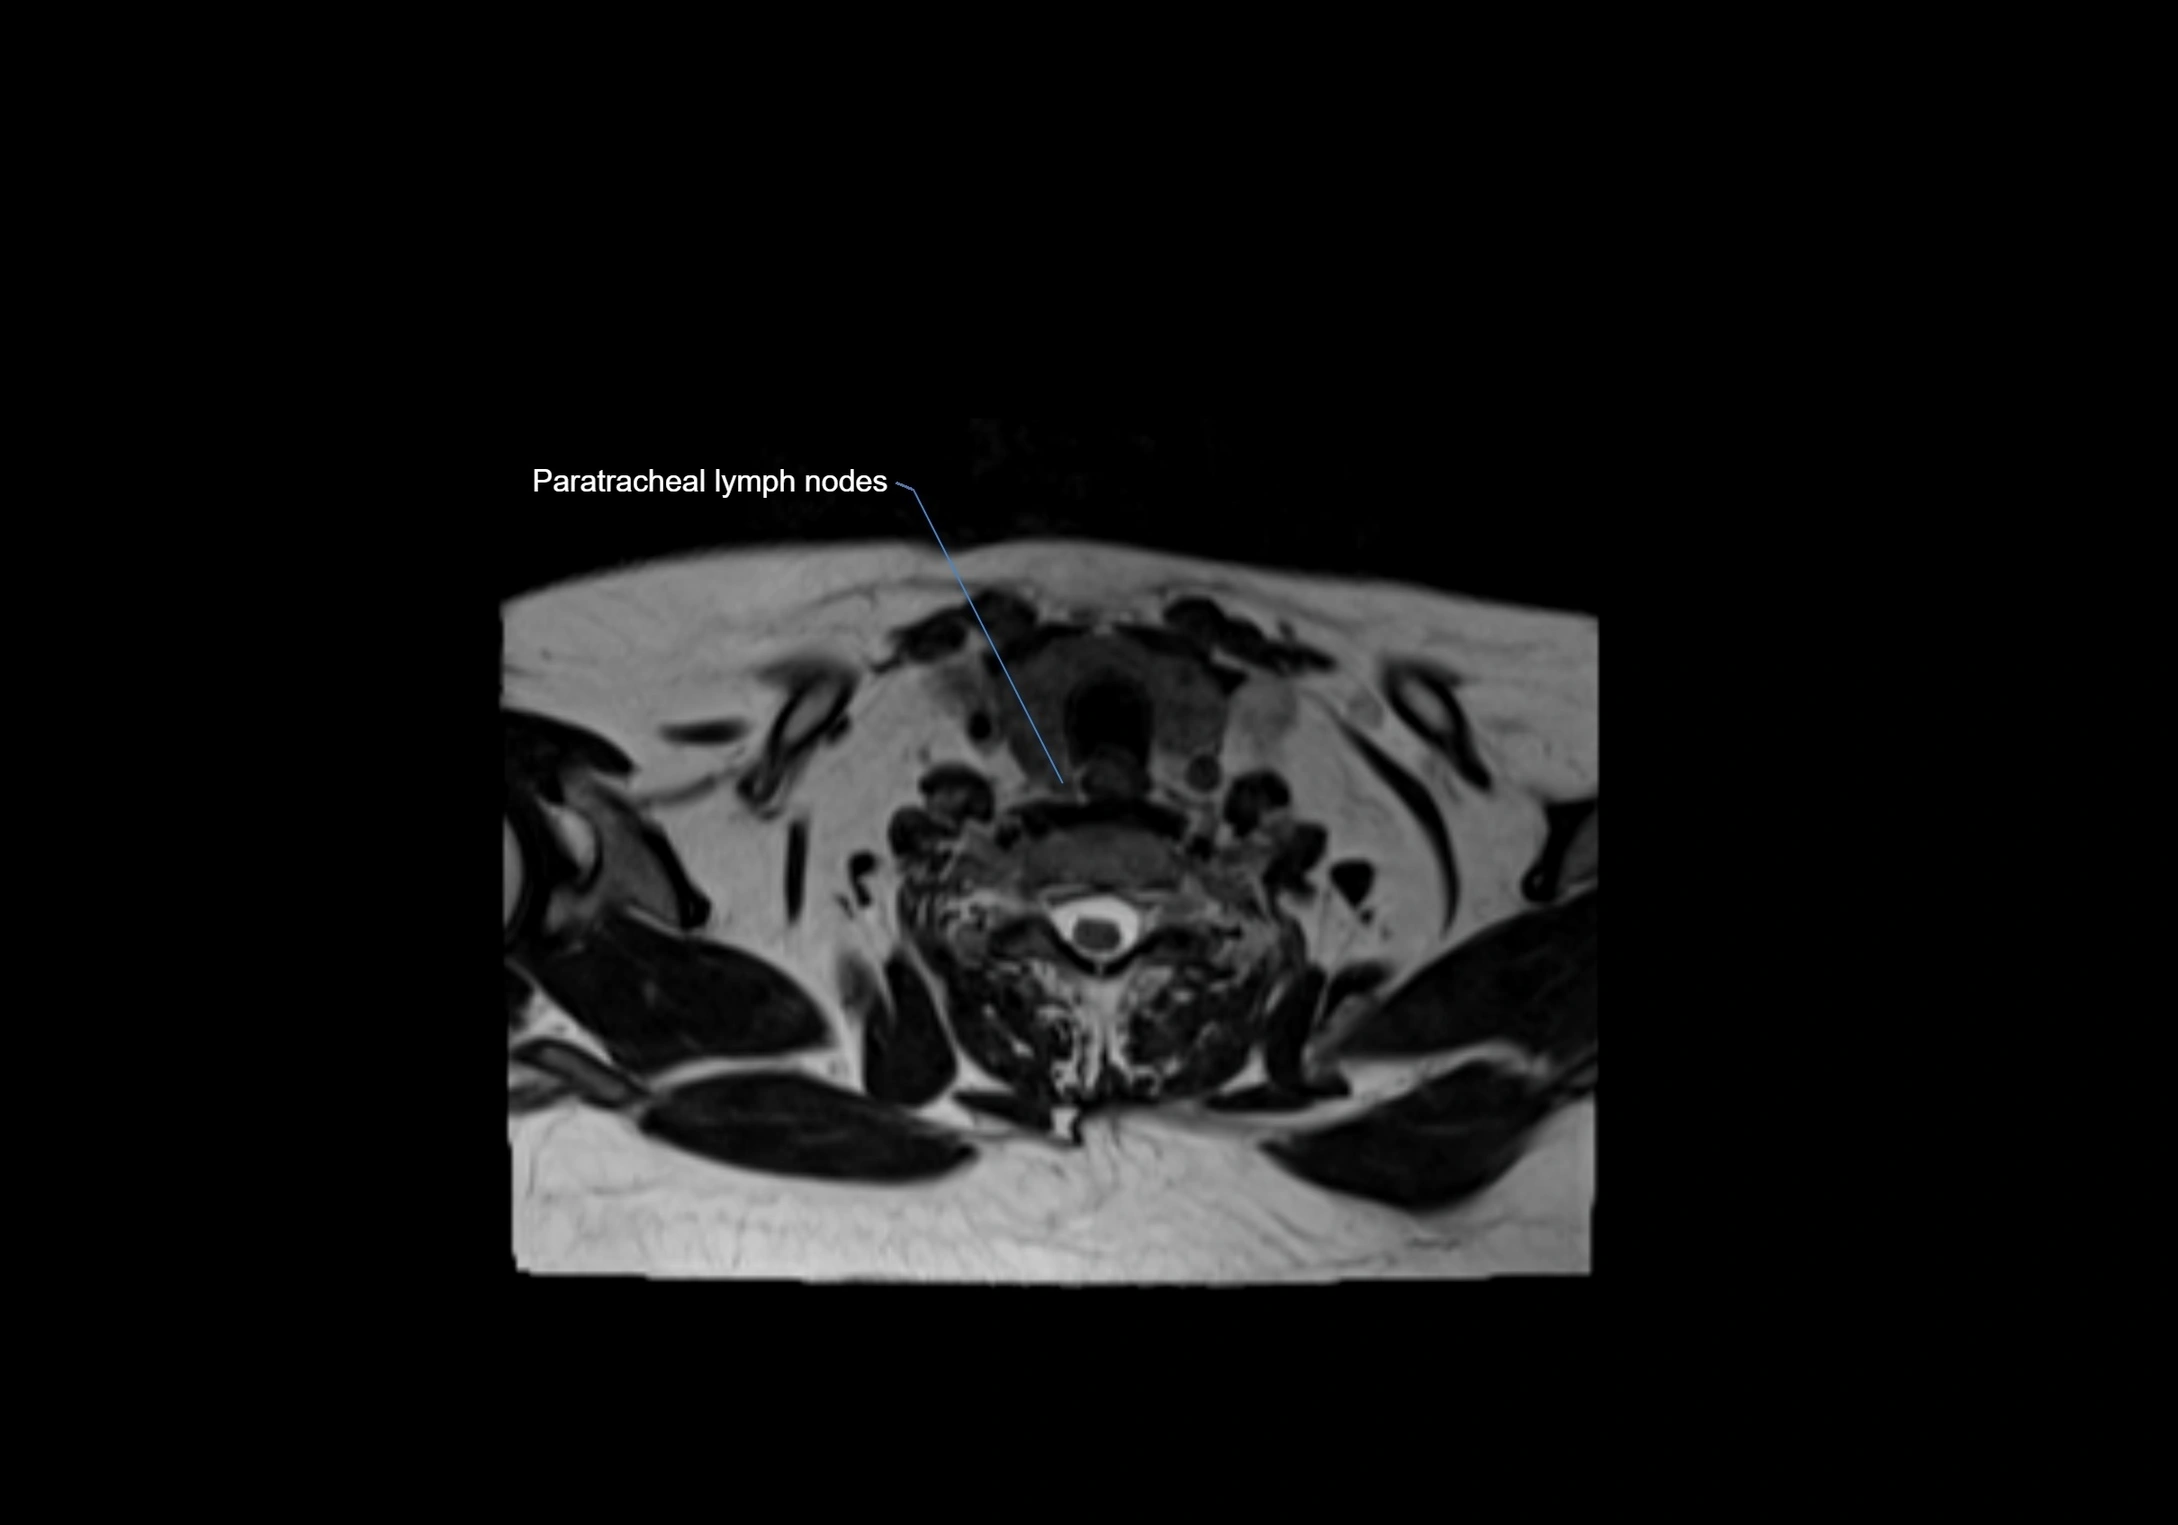

MRI Appearance

T1-weighted images:

• Normal accessory nodes appear as small, oval hypointense to intermediate signal structures within subcutaneous fat

• Surrounded by hyperintense fat, enhancing contrast for visualization

• Pathological nodes may appear enlarged or rounded, sometimes with cortical thickening

MRI images

image